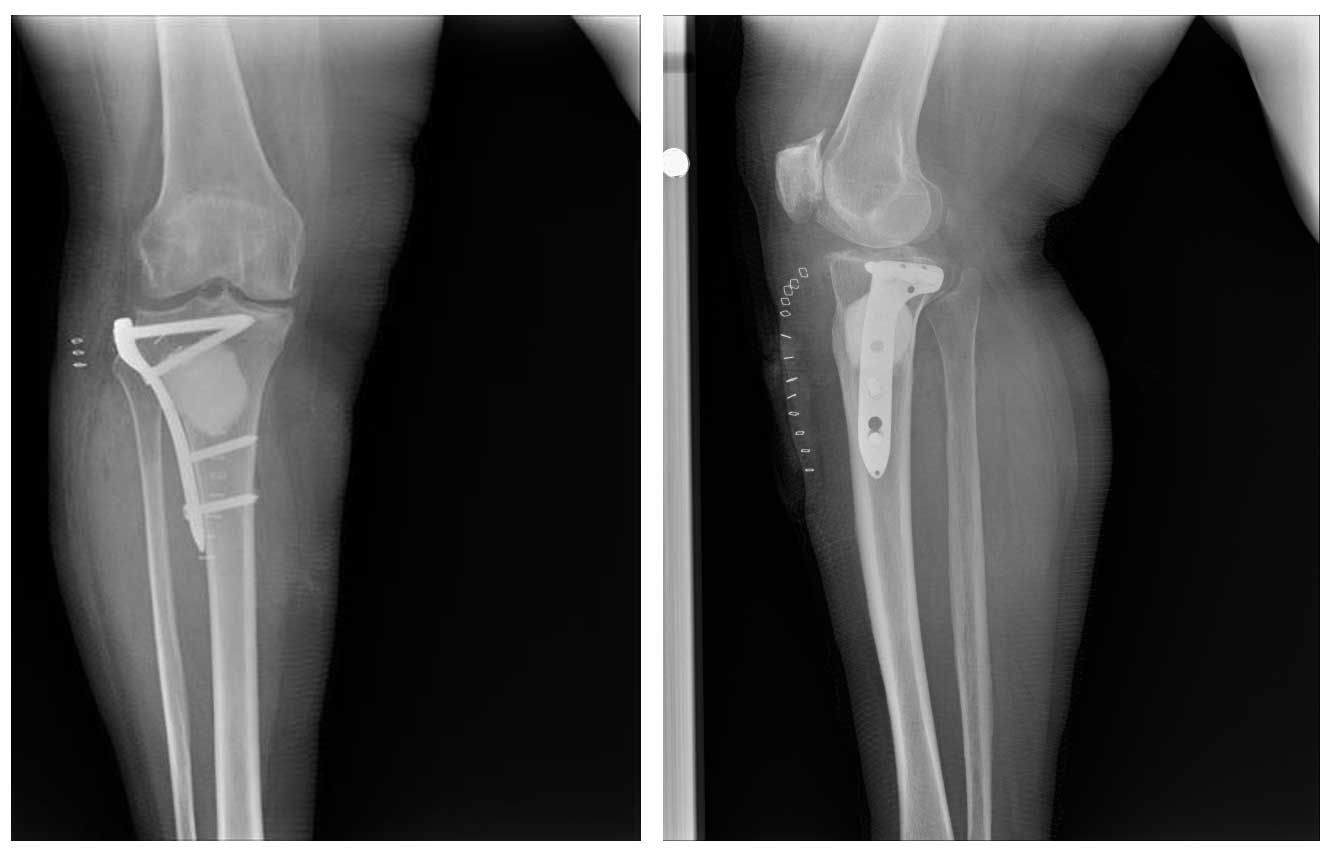

Ameliyat Sonrası: Röntgende çıkarılan tümör dokusu yerine doldurulan kemik çimentosu ve anatomik plak ile fiksasyon görülmekte.